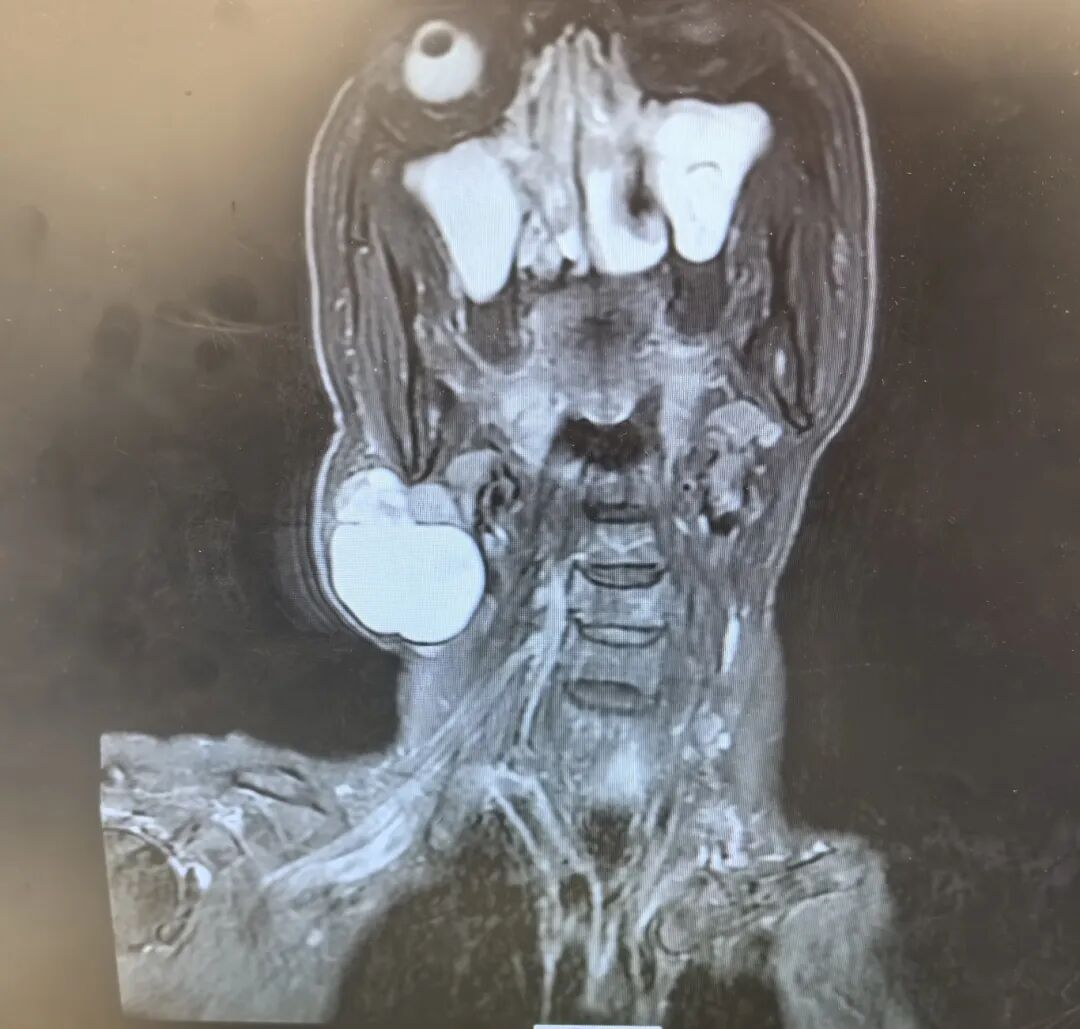

71 岁的韩女士右侧颈部曾有一处 0.5cm×0.5cm 的包块,十年间无明显变化,本未引起过多关注。然而1年前,这颗 “安静” 的肿物毫无征兆地快速生长,最终增大至 8.0cm×8.0cm,给韩女士的生活带来严重困扰,随即前往西安市红会医院耳鼻咽喉头颈整形修复科就诊。

门诊接诊的李莹医生详细询问病史并完善核磁等相关检查,结合影像学结果与临床评估,以 “右侧腮腺区肿物”

将韩女士收治入院。随后,龚龙岗主任、马戈主任医师带领团队对患者病情展开全面研判:考虑到肿物体积较大且生长特性特殊,为确保手术彻底性并最大程度保护面神经功能,最终确定实施

“右侧颈部肿物切除术+右侧腮腺部分切除术+面神经松解术”。

术前

核磁